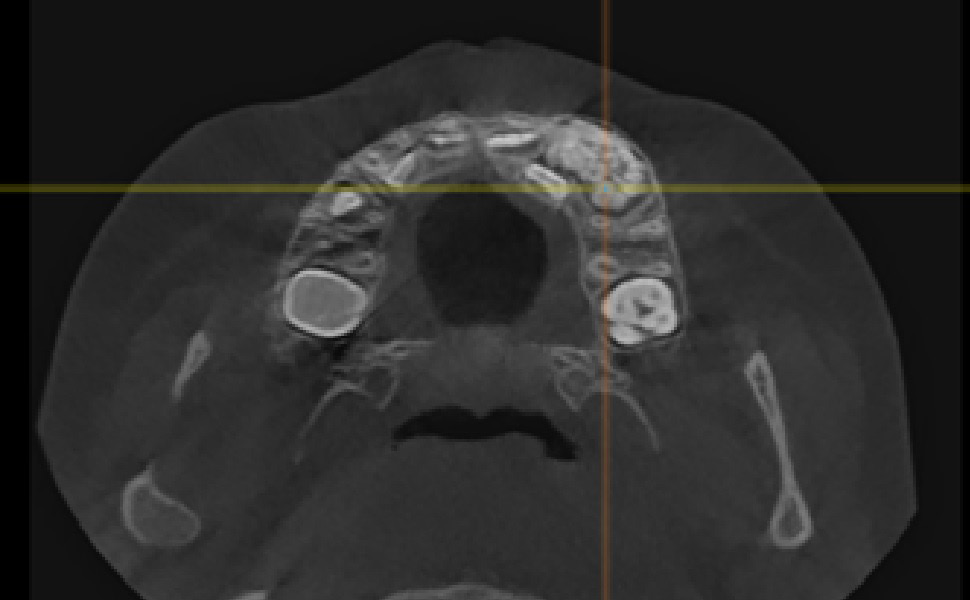

In 11 patients (55%), odontomas occurred in the maxilla – 4 (20%) in the midline, 5 (25%) on the left side (Figure 2) and 2 (10%) on the right side, and they were all OCp, of which 1 (5%) on the right side was an erupted odontoma. Nine patients (45%) were diagnosed with lesions in the mandible, with 5 (25%) of them having lesions on the right side (including 4 (20%) OCp and 1 (5%) OC) (Figure 3), 3 (15%) of them with lesions on the left side (1 (5%) OCp, 1 (5%) OC and 1 (5%) erupted odontoma) and 1 patient (5%) with OCp in the area of incisors.

Recently, there has been improvement in X-ray diagnostic imaging methods, especially with regard to CBCT, which certainly facilitates arriving at diagnosis as early as at the stage of radiological examination. Jayam et al. describe a case of an 11-year-old girl with a radiological picture (panoramic radiography, a tooth X-ray and a maxillary occlusal radiograph) description of impacted tooth 11 with an additional cusp and an extensive dentigerous cyst.2 In the course of marsupialization, the dentigerous cyst was found to have no contact with tooth 11, while it contacted the adjacent additional cusp. On histopathological examination, OCp was diagnosed with a cyst. According to some authors, X-ray images – panoramic radiographs and targeted dental X-rays – may not accurately reveal the pattern of the lesion, which is why cross-sectional CBCT is recommended in the case of doubts or for more accurately determining the location.2 In the case of 2 of our patients, it was not until a CBCT was performed that the adequate diagnosis was reached, and it was later confirmed during the procedure and histopathological examination. The first patient was a 9-year-old girl referred to an orthodontist in our clinic due to impacted tooth 21 for the exposure of the tooth and the application of a bracket to the crown of tooth 21. The patient had with her a current panoramic radiograph with visible impacted tooth 21, showing a small non-distinctive radiopacity in the tooth crown, which could be consistent with an additional cusp. An X-ray of tooth 21 was performed at our clinic, revealing a non-distinctive area of radiopacity next to the crown of tooth 21 (Figure 7). The patient was referred for cross-sectional CBCT. After verification, OCp was diagnosed and removed with its capsule, and an orthodontic bracket was attached to tooth 21 in local anesthesia (Figure 8). Histopathological examination confirmed the preliminary diagnosis of OCp. The other patient was a 5-year-old girl who was admitted to our clinic with a missing deciduous tooth 65. The patient had a current panoramic radiograph with her, revealing an impacted tooth (most probably tooth 65) with a non-distinctive area of radiopacity (Figure 9). Cross-sectional CBCT was recommended. In the X-ray image, the preliminary diagnosis suggested OCp with the impacted deciduous tooth 65 above it and the tooth bud of permanent tooth 25 on the palatal side (Figure 10). The procedure involved the resection of the impacted deciduous tooth 65 and the enucleation of the odontoma with its capsule; the tooth bud of tooth 25 was left. Due to the child’s age and her poor cooperation, the procedure was carried out in general anesthesia. Histopathological findings revealed OCp.